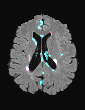

In recent years, data-driven machine learning (ML) methods have revolutionized the computer vision community by providing novel efficient solutions to many unsolved (medical) image analysis problems. However, due to the increasing privacy concerns and data fragmentation on many different sites, existing medical data are not fully utilized, thus limiting the potential of ML. Federated learning (FL) enables multiple parties to collaboratively train a ML model without exchanging local data. However, data heterogeneity (non-IID) among the distributed clients is yet a challenge. To this end, we propose a novel federated method, denoted Federated Disentanglement (FedDis), to disentangle the parameter space into shape and appearance, and only share the shape parameter with the clients. FedDis is based on the assumption that the anatomical structure in brain MRI images is similar across multiple institutions, and sharing the shape knowledge would be beneficial in anomaly detection. In this paper, we leverage healthy brain scans of 623 subjects from multiple sites with real data (OASIS, ADNI) in a privacy-preserving fashion to learn a model of normal anatomy, that allows to segment abnormal structures. We demonstrate a superior performance of FedDis on real pathological databases containing 109 subjects; two publicly available MS Lesions (MSLUB, MSISBI), and an in-house database with MS and Glioblastoma (MSI and GBI). FedDis achieved an average dice performance of 0.38, outperforming the state-of-the-art (SOTA) auto-encoder by 42% and the SOTA federated method by 11%. Further, we illustrate that FedDis learns a shape embedding that is orthogonal to the appearance and consistent under different intensity augmentations.